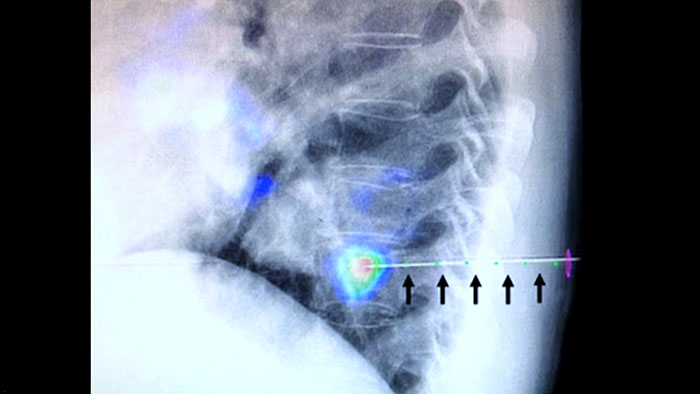

Lesion heterogeneity and lack of conspicuity limit the quality of specimens as well as the feasibility of biopsies when performed under ultrasound or conventional CT. With the increasing adoption of screening programs in lung, early lung cancers manifesting as small nodules have been detected more frequently than ever before. 14.5% of a screened population was observed to have nodules ≤10 mm.1-2 Our needle navigation technology with CBCT increases precision, and enables the targeting of smaller (<=1 cm) or heterogeneous lesions more accurately with less needle repositioning and at lower dose than conventional CT.1-2

compared to conventional CT 1

Less needle repositioning compared to conventional CT 1

Lower skin dose compared to conventional CT 1

XperGuide provides highly accurate live image guidance of each needle to a targeted position by overlaying pre-planned trajectories with fluoroscopic imaging.3